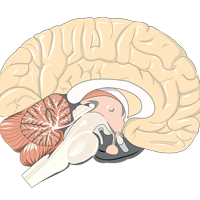

Know Your Anatomy